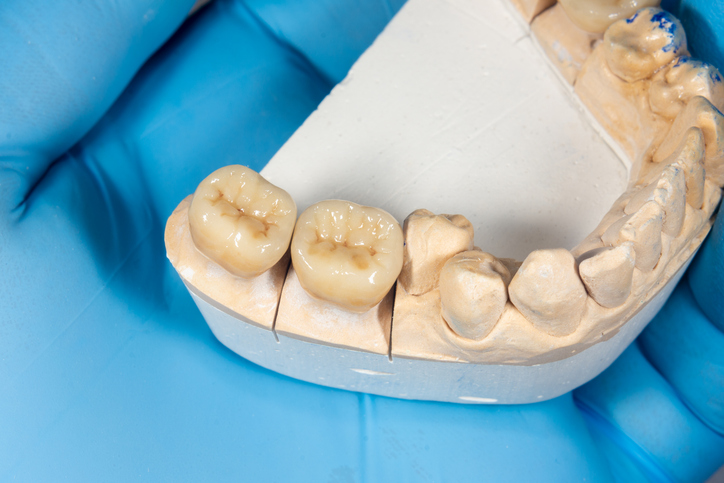

3. X-ray로도 보이지 않는 초기 충치

충치는 어느 날 갑자기 생기지 않습니다. 보통 충치가 X-ray에서 보이려면 치아의 50% 이상이 부식되어야 합니다.

그 전까지는 스스로 관리하면서 예방해야 하며, 6개월 주기의 정기 검진이 권장됩니다.

검진 때 발견되지 않았다고 해서 안심해서는 안 되며, 생활 습관을 바꾸고 치아 관리를 더욱 철저히 해야 합니다.